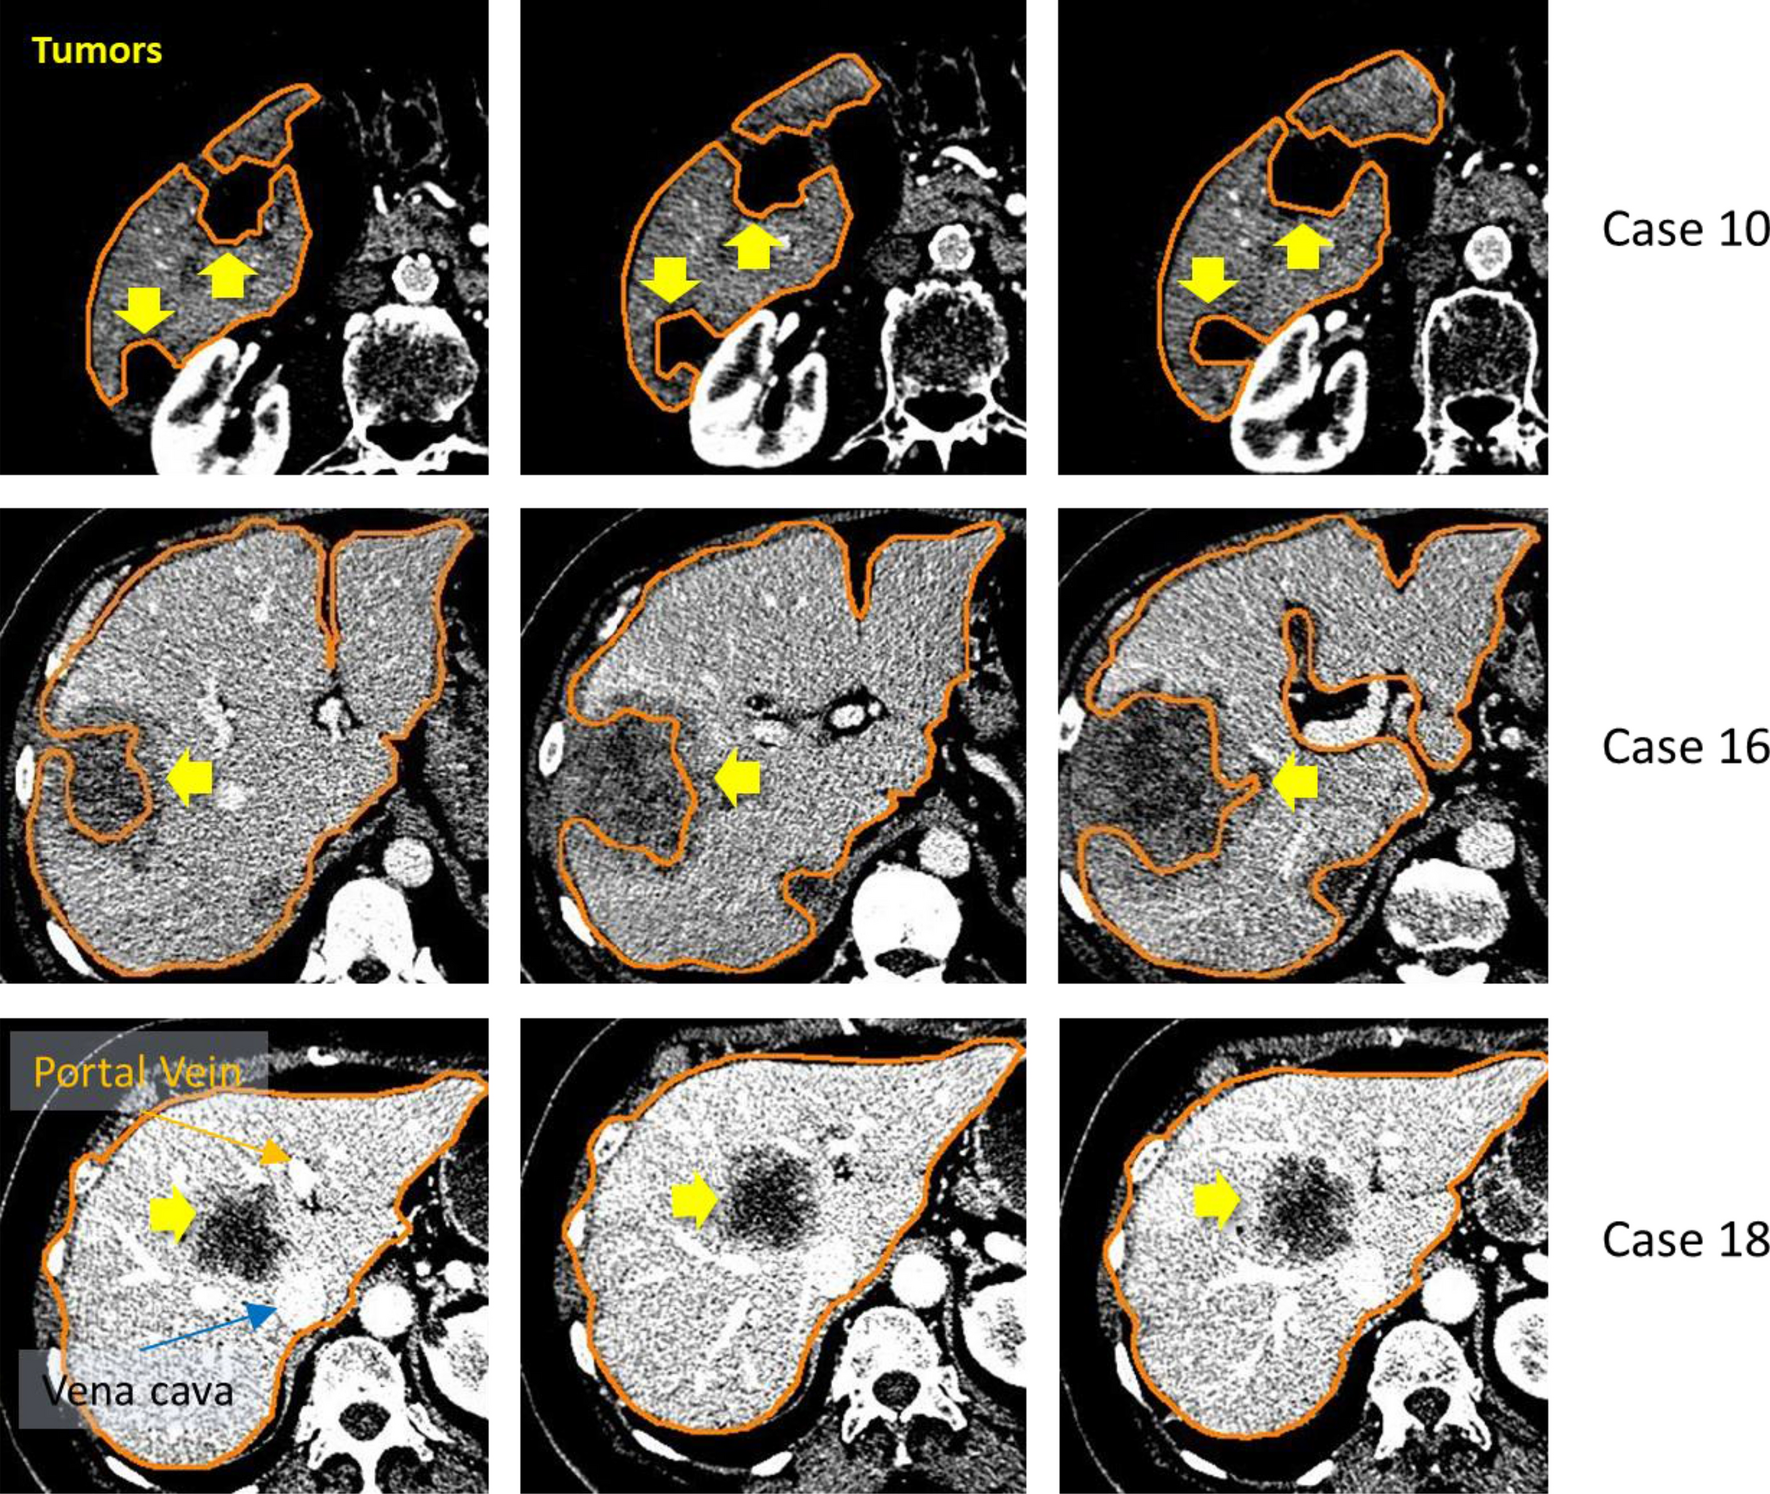

Segmentations of diseased livers. For the case number 18 (included in Table 4 but not in Table 9), the lesion was relatively small and located inside the liver, near vena cava and portal vein entry.